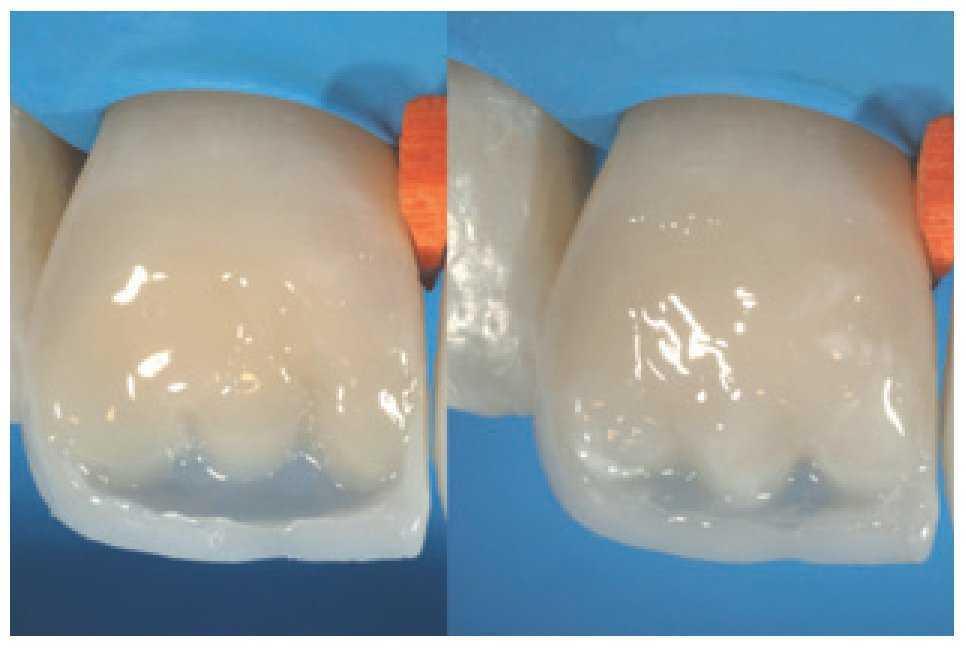

Figura 18a y b Para conseguir una restauración estéticamente atractiva es importante controlar de forma concienzuda las capas de dentina y esmalte.